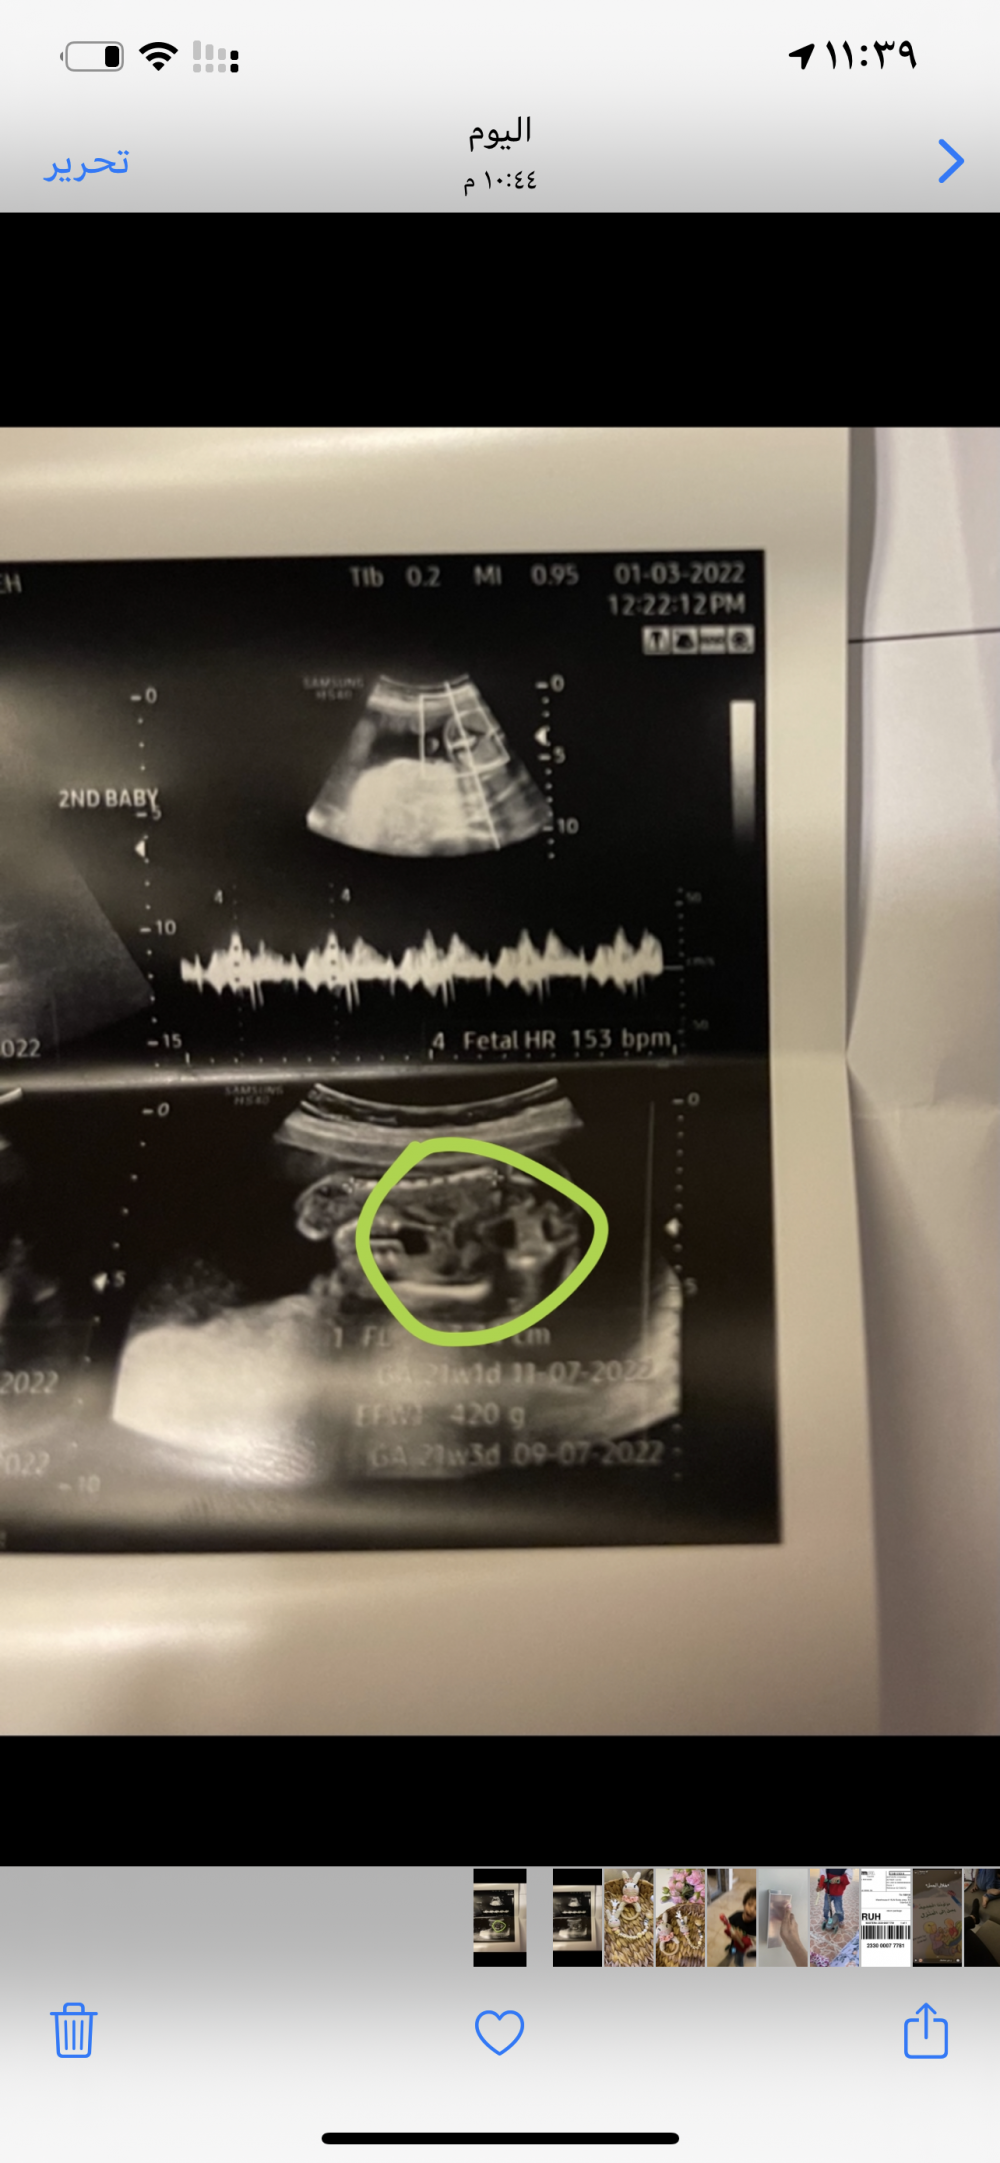

الحمد لله توي راجعه من الدكتوره وقالت لي اننا بنوته لونوني بس مدري انا مو واثقه بسونارها لكن الاسابيع الجايه ان شاء الله اتاكد 💓💓💓💓

هو الدكتور قلي وضعيه السحود اللي فهمت انو دي يداتها اللي بين الرجول بس قلي شوفي مافي بروز احتمال بنت والبيبي التاني كان واضح جدا البروز ولد 🥲